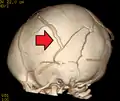

الإصابات المميزة المرتبطة بمتلازمة الرضيع المهزوز التي من ضمنها نزيف في شبكية العين وكسور متعددة في العظام الطويلة وورم دموي تحت الجافية (نزيف في الدماغ). وقد تطورت هذه العلامات على مر السنين كعلامات متعارف عليها لإساءة معاملة الأطفال متلازمة الرضيع المهزوز. اخصائيين الطب يشتبهون وبقوة أن الهز هو السبب في إصابة الطفل الرضيع أو الطفل الصغير بنزيف في شبكية العين وكسور وإصابة الأنسجة اللينة أو ورم دموي تحت الجافية، والتي لا يمكن تفسيرها من خلال الصدمات العرضية أو الحالات الطبية الأخرى. نزيف شبكية العين يحدث في حوالي 85% من حالات متلازمة هز الطفل. نوع النزيف في شبكية العين يعتبر ميزه مفيدة جداً في تحديد التشخيص، حيث أن هناك العديد من الأسباب الأخرى لنزيف شبكية العين غير متلازمة الرضيع المهزوز، وعادة ما تكون هناك نتائج إضافية (عينية و/أو المنهجية) التي تجعل التشخيصات الأخرى واضحة. كسر الفقرات والعظام الطويلة والضلوع قد تكون ايضاً مرتبطة بمتلازمة الرضيع المهزوز. كما أفاد الدكتور جون كافي في عام 1972 ان الأفولسيونس ميتافيزيل (وهي شظايا صغيرة من العظام قد يمزق فيها السِمحاق وهي جلدة أو قشرة رقيقة تغطي عظم الرأس والعظام القشرية) وذلك يؤثر على العظام بشكل عام سواء كانت العظام القريبة والبعيدة من الرأس " كعظام الركبة خاصة". ومن الأثار الشائعة ايضا بسبب متلازمة الرضيع المهزوز إصابة المحور العصبي، وعدم وصول الأكسجين وتورم الدماغ، وهذا قد يؤدي ايضا لارتفاع الضغط داخل الجمجمة وتلف الأنسجة الحساسة في المخ. والمصابين بمتلازمة الرضيع المهزوز قد يعانون من التهيج، وفشل بالنمو، واضطرابات في أنماط الأكل والشعور بالخمول والتقيؤ والشعور بنوبه واليافوخ اأو المنتفخه وهي (بقع ناعمة تظهرعلى رأس الرضيع)، وزيادة في حجم الرأس، وصعوبات في التنفس، وإتساع في حدقة العين .

في عام 1971، قال الدكتور نورمان قوثكلش أن الإصابة تسبب نزيف تحت الجافية في الرضع والتي تمزق الأوردة في الغشاء الموجدود تحت الجافية. وتم إدخال مصطلح "متلازمة الرضيع المهزوز " من قبل الدكتور جون كافي . في عام 1973، ووصف طبيب أشعة الأطفال مجموعة الأعراض التي وجدت بالطفل المصاب مع الأدلة الخارجية على صدمات في الرأس، بما في ذلك نزيف في شبكية العين ونزيف داخل الجمجمة مع نزيف تحت الجافية أو تحت العنكبوتية أو كلاهما على انها متلازمة الرضيع المهزوز. وأنه قد تطورت التقنيات في التصوير المقطعي والتصوير بالرنين المغناطيسي من سنة 1970 إلى 1980 حيث تقدمت القدرة على تشخيص المتلازمة.